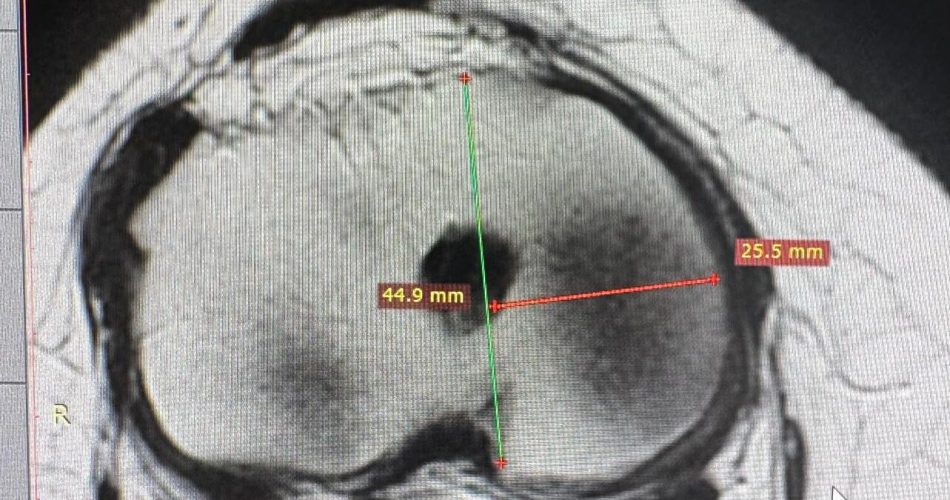

Una condizione che, nel tempo, aveva determinato dolore persistente e un progressivo sovraccarico articolare del ginocchio. “Il trapianto meniscale – spiega Moretti – rappresenta una procedura altamente specialistica che consente di ripristinare la funzione biomeccanica del ginocchio. La tecnica da noi utilizzata ha previsto l’impianto di un menisco proveniente da donatore senza l’utilizzo di plug ossei”.